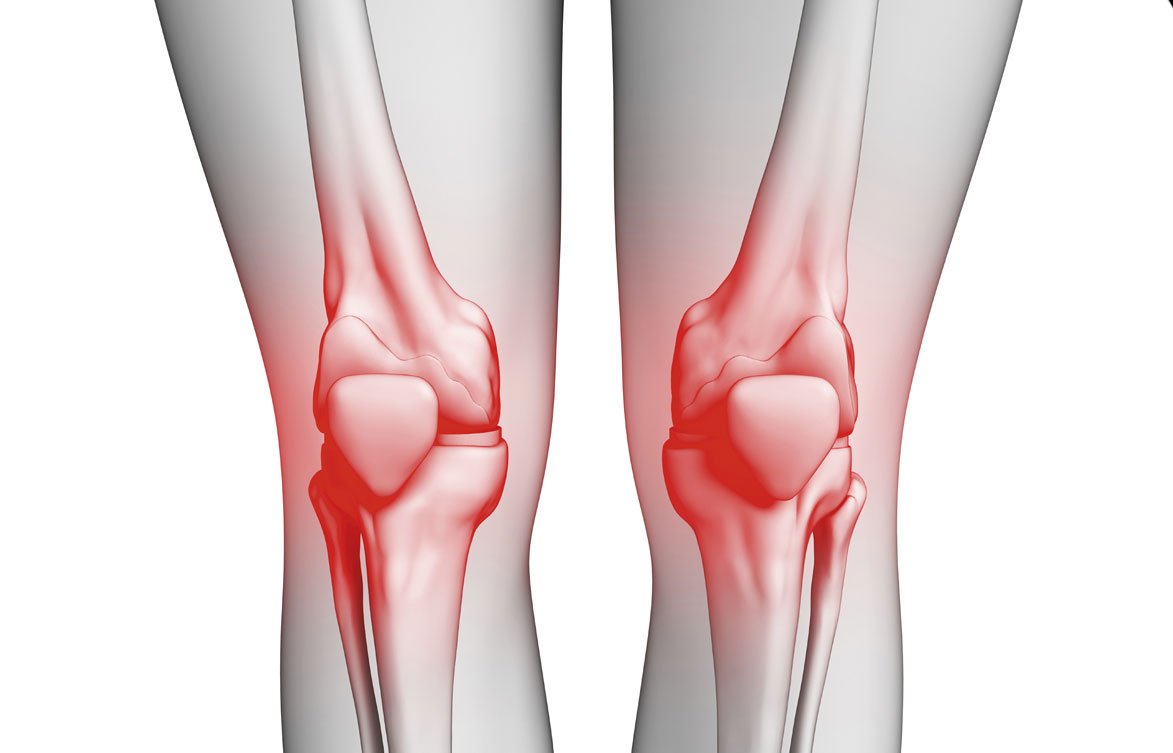

Knee osteoarthritis is a condition that occurs when the cartilage in the knee joint wears down, causing bones to rub against each other. This wear and tear is one of the most common causes of knee pain and irritation, and includes symptoms such as:

- Swelling and redness in the affected area.